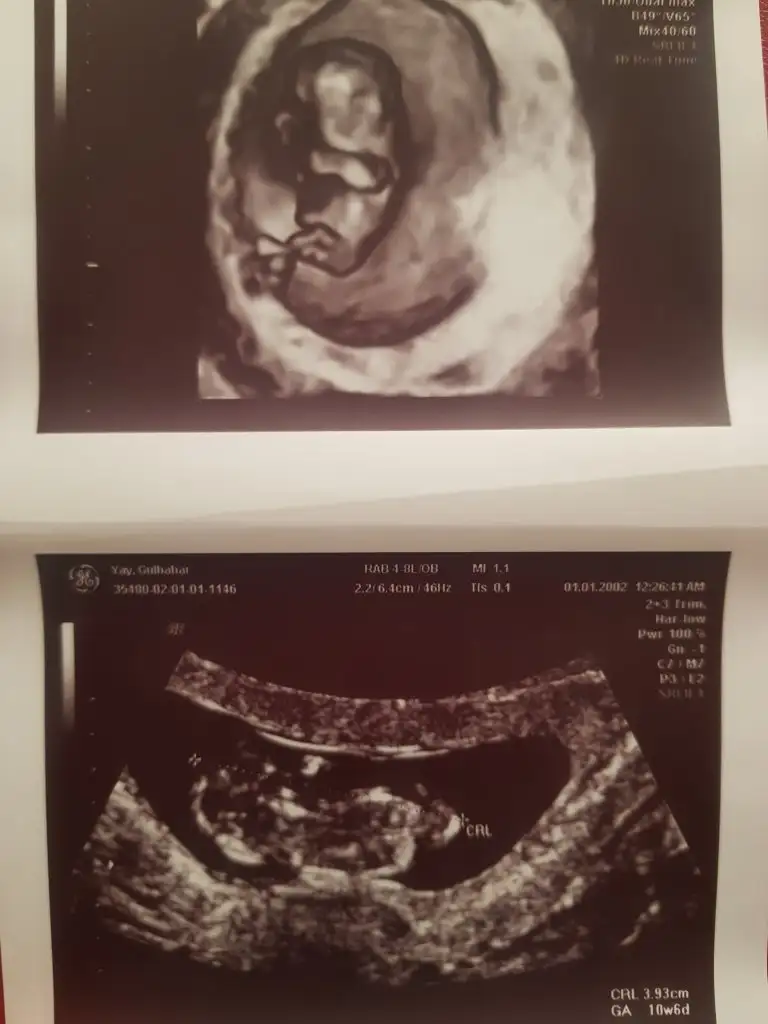

Burda sizce ne :) buda baska bi foto 11+3

Hayirlisi birde bu var ama bence burdada belli degildir :)Karanlik kalmiş usg sanki paralel gibi nubu eminde değilim![]()

Sizinmi usg burada dik görünüyor nubu pozisyon gercekten çok degişiyor usg deHayirlisi birde bu var ama bence burdada belli degildir :)

Evet cnm buda benim... dedigin gibi cok degisiyor :) merak ediyoruz bakalim hayirlisiSizinmi usg burada dik görünüyor nubu pozisyon gercekten çok degişiyor usg de![]()

Bunlarda 10+6 haftalıkken11 haftasınıda paylaşırmısınız sanki erkek gibi gibi